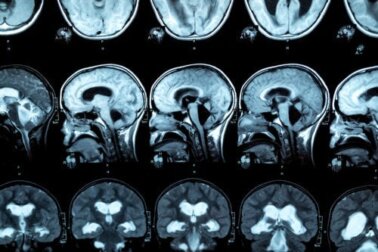

Sie ist durch eine Demyelinisierung und schließlich Nekrose des Corpus Callosum gekennzeichnet. Was bedeutet das? Der Corpus callosum ist eine Struktur im Gehirn, die die beiden Gehirnhälften miteinander verbindet und dazu beiträgt, dass beide koordiniert arbeiten.

Auf bildgebenden Untersuchungen des Gehirns kann auch eine Schwellung des Corpus callosum zu sehen sein. Darüber hinaus liegen in einigen Fällen Anzeichen eines interhemisphärischen Diskonnektionssyndroms vor.

Um diese Pathologie zu diagnostizieren, wird eine MRT-Untersuchung durchgeführt, um Läsionen im Corpus callosum zu erkennen. Denn Untersuchungen haben ergeben, dass Menschen mit Alkoholproblemen eine Verringerung der vorderen, mittleren und hinteren Dicke des Corpus Callosum sowie Veränderungen in der Größe des Frontallappens und der kortikalen Sulci aufweisen.